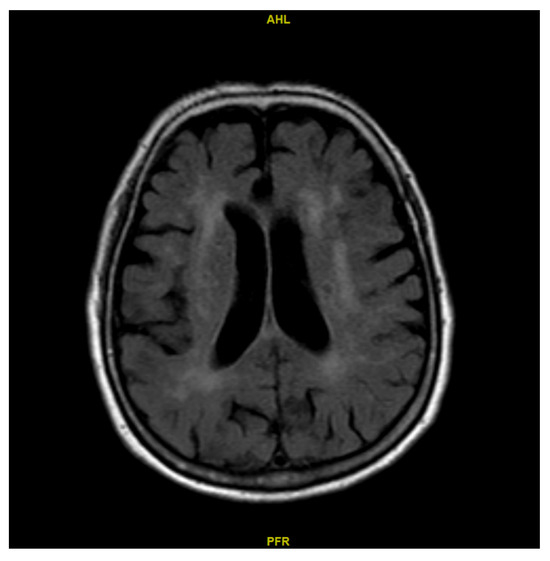

2.2. Determination of the Lateral Ventricle Volume of Both Sides

3.2. Comparison Between CBF on the Side of the LLV and the Side of the SLV Across the ROIs